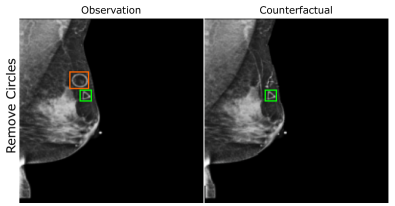

EMBED

Using prior insights, we apply our mechanisms to a real-world artefact removal task on the EMory BrEast imaging Dataset (EMBED) (Jeong et al., 2022). Schueppert et al. (2024) observe that triangular and circular skin markers are spuriously associated with breast cancer in classifiers due to shortcut learning (Geirhos et al., 2020), and manually labelled 22,012 affected mammograms. Using this dataset, we train a significantly scaled-up, amortised, anti-causally guided semantic mechanism () to remove skin markers. We model triangular markers (), circular markers (), breast density (), and cancer () as independent parents of the mammogram , and remove artefacts by intervening on and while holding and fixed. Figure 6 shows that our mechanisms effectively remove artefacts and can disentangle representations for triangles and circles. We successfully remove of triangles and of circles in our test set - a noteworthy result given the dataset’s small size and the scarcity of labelled skin markers (Appendix I).